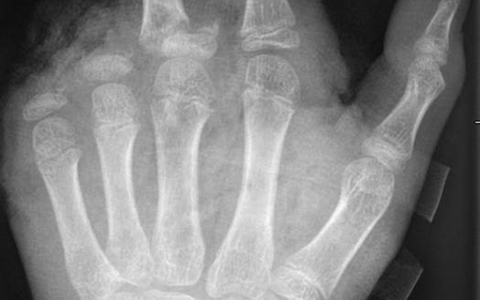

In der Handchirurgie müssten an Silvester im Unfallkrankenhaus rund 20 bis 40 Menschen mit Böllerverletzungen operiert werden, sagt die Ärztin. Dieses Jahr werde sie mir vier weiteren Handchirurgen im Einsatz sein. Die häufigsten Verletzungen entstünden durch explodierende Böller in der Hand.

«Der überwiegende Teil der Verletzungen trägt tatsächlich lebenslange Folgen mit sich, weil die Sprengkraft dazu führt, dass eben nicht nur einzelne Strukturen verletzt sind, sondern immer mehrere. Und das heilt praktisch nie ganz folgenlos ab.» Zum Teil könnten Hände nicht mehr gerettet und müssten amputiert werden.